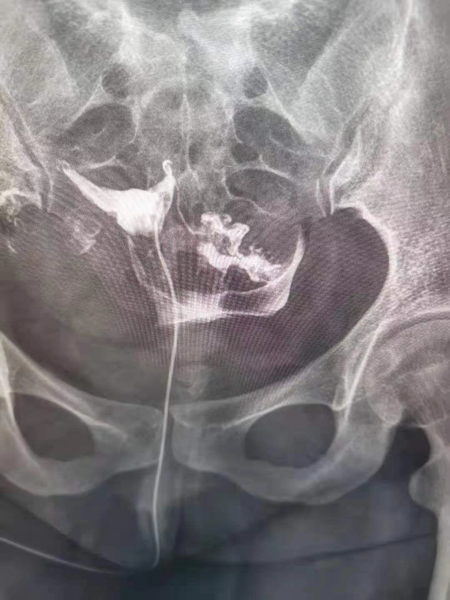

1.造影成像的圖像質量清晰直觀,臨床醫生可以通過讀片來判斷子宮輸卵管腔內的狀態,清晰的圖片對于炎癥、積水等異常診斷更為準確,降低了漏診率和誤診率,對下一步不孕癥的處理方向提高幫助。

2.診斷同起到治療作用,輸卵管內的炎癥碎片、粘液栓、細小的纖維絲均可引起輸卵管的閉塞,并且輸卵管腔內有復雜的皺襞樣結構,造影劑在通過輸卵管腔時,可通過沖刷疏通的作用,改善輸卵管腔內的粘連堵塞,為精子和卵子的運送提供暢通的道路,還可以恢復腔內纖毛的活動,為運送受精卵做好準備。